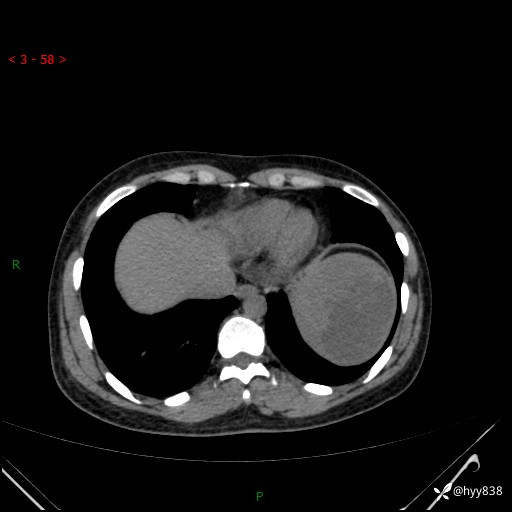

患者性别:男

患者年龄:44岁

主诉:外院超声发现脾脏占位,来我院进一步诊治。

临床诊断:脾脏占位

脾脏CT平扫+增强(动脉期+静脉期)